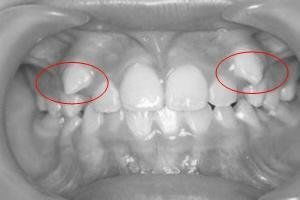

一般多生牙的產(chǎn)生的危害就是若長在牙列里,就會占據(jù)正常牙的位置,由于正常牙受到多生牙的排擠,只好從牙齦的旁邊長出去,導(dǎo)致牙齒排列紊亂。若多生牙長在牙列的外邊,就會形成雙層牙,兩牙之間有縫隙,造成食物殘渣滯留和嵌塞,導(dǎo)致牙齦組織發(fā)炎,甚至還會引起齲齒的發(fā)生。這樣最好是及時進行拔掉。

多生牙本來就是不應(yīng)該有的牙齒,而且還可能造成不良的后果。所以一旦發(fā)多生牙,就應(yīng)該及時請醫(yī)生鑒別并拔除。但是,仍有少數(shù)兒童在多生牙的生長早期未被引起注意,而發(fā)現(xiàn)后長在牙列中排列還算整齊,又不影響其他牙齒,咬合關(guān)系也未出現(xiàn)異常情況時,可以考慮保留這個多生牙。